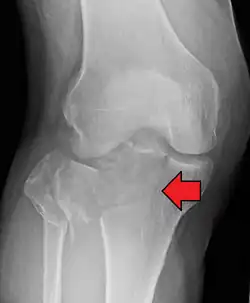

Lipohemarthrosis (presence of fat and blood from bone marrow in the joint space after an intraarticular fracture) seen on X-ray in a person with a subtle tibial plateau fracture -

Lipohemarthrosis due to a tibial plateau fracture -

Subtle tibial plateau fracture on an AP X ray of the knee -

A tibial plateau fracture seen on X-ray